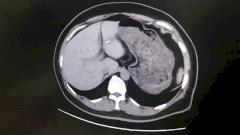

Во владивостокской клинической больнице № 2 провели сложную операцию пациенту — удалили злокачественную опухоль из почки и при этом сохранили рабочий орган. К медикам он попал в тяжелом состоянии в конце прошлого года. Врачи осознали, что жизнь мужчине спасет только сложная операция.